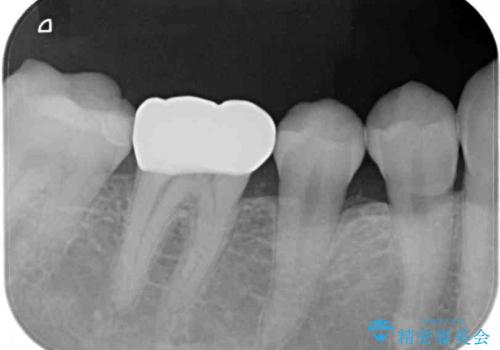

- セラミッククラウンが度々欠けてしまうとのことで来院された患者様です。

セラミッククラウンを装着するには、削る量がやや少ない印象であったので、クラウン破折リスクを回避するために削る量を少し増やすこととしました。

また、咬合力が強いため、強化セラミックのみで製作するフルジルコニアクラウンにて補綴治療することとしました。

フルジルコニアクラウンは、強度が高い反面、審美性に欠けるため、前歯部に装着することはお勧めできません。